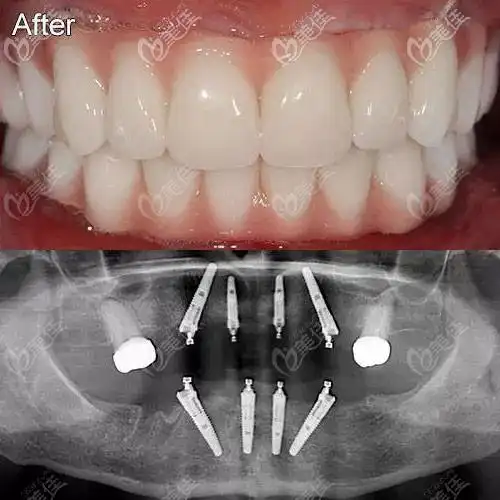

70岁老人在北京瑞泰口腔丰台医院用4颗种植体解决了半口牙缺失